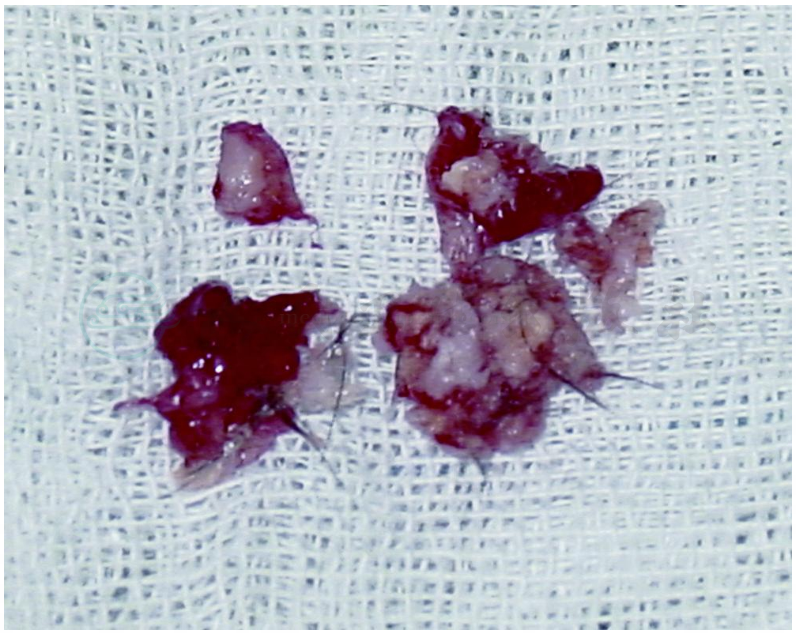

图27患者经鼻手术切除标本

可见皮脂、皮肤及毛发